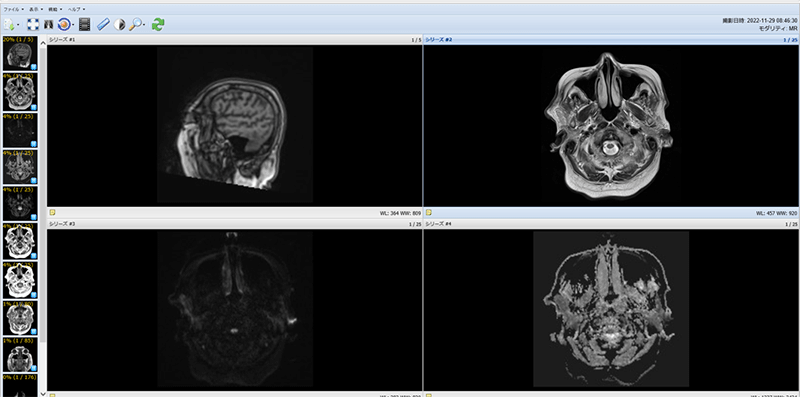

実際の画面の一例

MRI画像